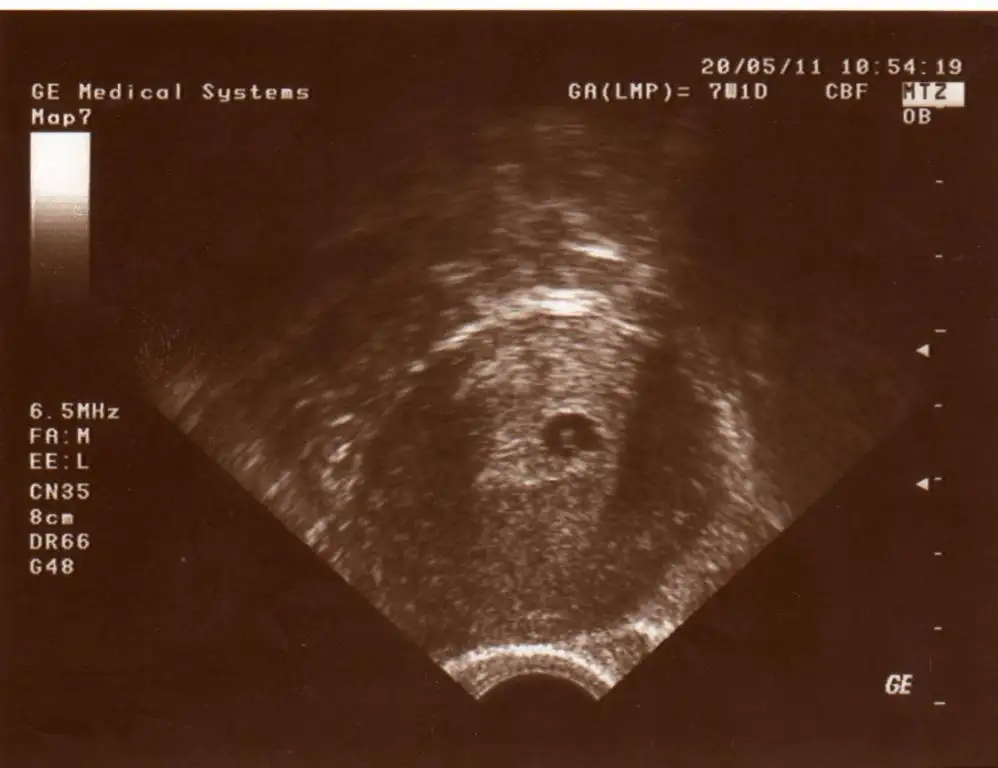

arkadaşlar benim bebeğim 6 haftalık olması gerekirken 4 haftalıktı ve hiç bişey görünmüyordu kesede dr problemli bir gebelik olurdu zaten dedi bu kadar erken olan düşüklerde müdahale etmek yersiz dedi vücudumuz kendisi atıyormuş zaten bende çok üzülmedim açıkcası sadece yıprandım çünkü problemli bir bebek ve problemli bir gebeliğin çok çok daha kötü eksileri olabilir hayatta kısmet daha sağlıklı bir gebeliğe inşallah hepinize çok teşekkür ederim arada atladığım arkadaşlarım olursa kusura bakmayın bir geçmişolsun bile insana çok iyi geliyor inanın :)

7+2 de kalp atışlarını duyduk çok şükür

Ne yazık kı bugun doktorum kesenın ıcınde bebegı yıne goremedı ve kurtaj olman gerekıyo dedı